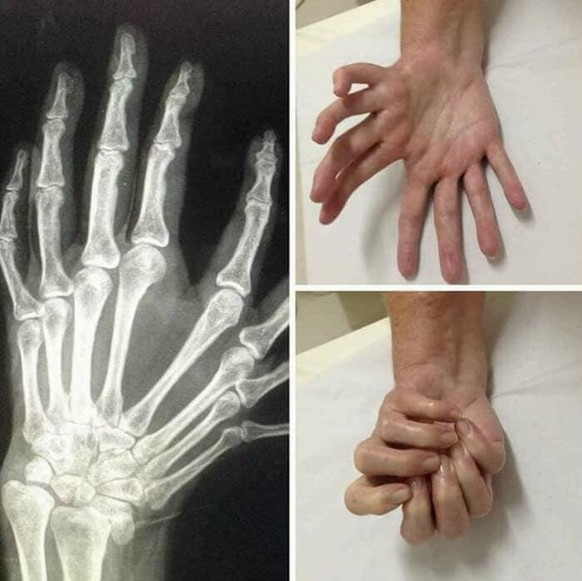

Milchzähne und bleibende Zähne haben wir alle. Nicht aber die seltene Fehlbildung Ulnar dimelia (auch mirror hand syndrome genannt).